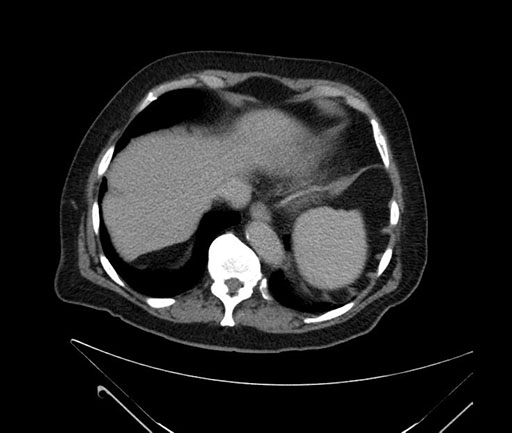

Whipple (pancreaticoduodenectomy) [case 7]

Axial - stented

Imaging analysis

Based on your CT findings, which issue(s) would give reason for "planned slowing down moment(s)" in this case?

Considering a standard Whipple procedure, what step(s) of the operation would you do differently in this case?